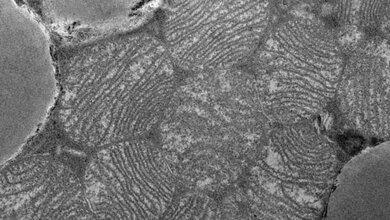

PKD1 ist eine so genannte Kinase – ein Enzym, das andere Enzyme auf eine bestimmte Weise chemisch modifiziert und sie so aktiviert oder hemmt. „Wir haben das PKD1 in Mäusen ausgeschaltet und diese dann sechs Monate lang auf eine sehr energiereiche Kost gesetzt“, erklärt Löffler. „Die Tiere aßen zwar genauso viel wie unbehandelte Artgenossen, nahmen dabei aber kaum zu.“ Normalerweise entwickeln Mäuse zudem bei kalorienreicher Ernährung mit der Zeit eine so genannte Insulin-Resistenz – die Vorstufe eines Diabetes. Bei diesen Mäusen war dieser Effekt nicht zu beobachten. Auch andere gesundheitliche Nebenwirkungen, wie etwa die Bildung einer Fettleber, blieben bei ihnen aus. Zugleich zeigten die Tiere einen deutlich erhöhten Energieumsatz. Die „Heizung-Zellen“ enthalten nämlich eine große Menge von Mitochondrien. In beigem Fettgewebe arbeiten die Mitochondrien im Leerlauf – sie produzieren nur Wärme.

Beige Fettzellen unterscheiden sich in ihrem Stoffwechsel also fundamental von ihren weißen Zellen. Da ist es kein Wunder, dass in ihnen auch ganz andere Gene aktiv sind. „Unsere Mäuse ohne PKD1 zeigten in ihrem Fettgewebe ein ähnliches Genaktivitäts-Muster, wie es eigentlich in beigen Fettzellen zu erwarten wäre“, betont Mona Löffler.